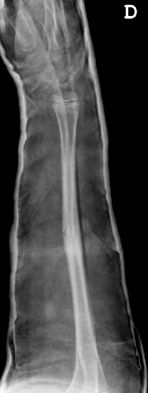

Las fracturas de ambos huesos del antebrazo al mismo nivel, con líneas de fractura oblicua-transversa o desplazamiento convergente son inestables y precisarán de tratamiento quirúrgico. En estos casos está indicado, dependiendo de la edad del paciente, el tratamiento mediante reducción y osteosíntesis. El enclavado intramedular elástico es el tratamiento de elección (Figura 15).

Figura 15: a-Imagen clínica de fractura de antebrazo derecho con gran deformidad. b- Radiografía donde se aprecia fractura de radio-cúbito de trazo transverso en el mismo nivel. c, d-Enclavado intramedular elástico. e,f- Imagen final con buena consolidación ósea.